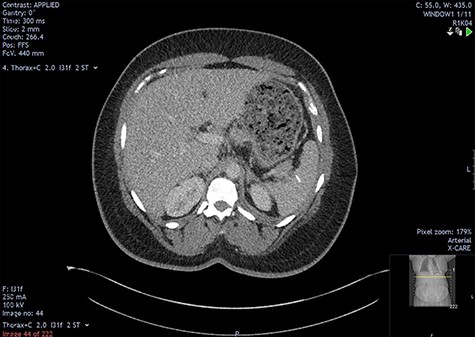

The initial bloods showed haemoglobin 121 g/l, white cell count 29.2x109/l, lactate 0.8 mmol/l, C-reactive protein 348 mmol/l and deranged alkaline phosphatase at 175 mmol/l, with other blood results in normal ranges. A diagnosis of intra-abdominal sepsis secondary to acute cholecystitis was suspected and initial resuscitation was commenced. A computerized tomography (CT) scan of the thorax, abdomen and pelvis demonstrated a mild left pleural effusion with bibasal subsegmental consolidation, splenic subcapsular haematoma, splenic hypodensity and a linear hyperdensity density crossing the upper anterior pole of the spleen, referred to hereafter as the foreign body (Figs 1–3).

Two-mm axial section from a CT scan showing the perisplenic haematoma (*) and hypodensity (arrow) separating the upper anterior pole of the spleen (p) from the body (b). CT section number 54.